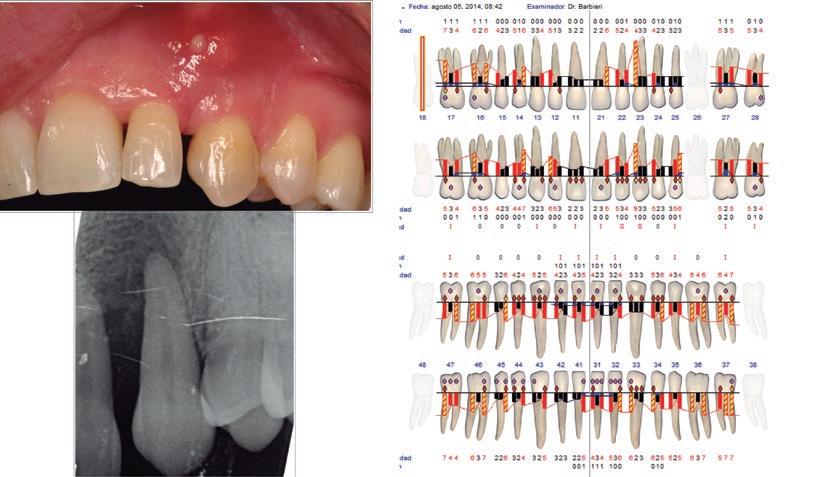

RMujer de 42 años médicamente sana. Acude a la clínica preocupada porque notaba una gran movilidad en el diente 23. Tratada ortodóncicamente cuatro años antes.

REstado periodontal a los dos meses de la terapia periodontal básica (raspado y alisado radicular).

SEvolución del caso a los dos años y medio, habiendo realizado únicamente raspado y alisado radicular unido a un control exhaustivo de la higiene oral.

P., Fuenmayor Fernández V. & Gil Loscos F. J. Regeneración periodontal en la practica clínica. Med Oral Patol Oral Cir Bucal 11, 382–392 (2006). Cortellini P. & Tonetti, M. S. Clinical concepts for regenerative therapy in intrabony defects. Periodontology 2000 68, 282–307 (2015). R Comparativa a los casi cuatro años en donde se evidencia un relleno radiográfico del defecto periodontal.